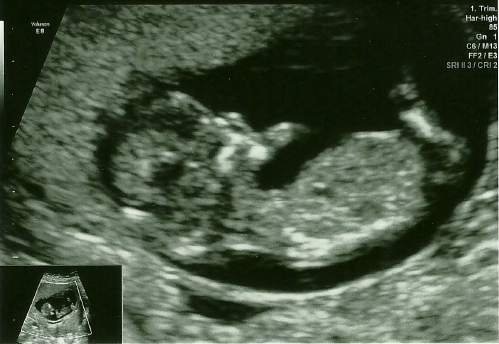

Scan went well today, got sent out in between to empty my bladder, as apparently it was too full... They didn't tell me whether the nuchal measurement is ok or not, I have to wait 2 weeks for the result. But they gave me my pregnancy notes and I found the measurement myself. A bit of research online and it seems to be fine. Some reassurance Smile

Oooh, Amanda and NoMore such lovely scan pics. Fabulous news! I'm so glad more are being posted.

Great scan pic nomore! Loving all of these pics, can't wait until my little blob looks more like a baby haha! I'll be happy to see a HB actually at this stage!

Ooo another lovely scan pic! Congratulations NoMore